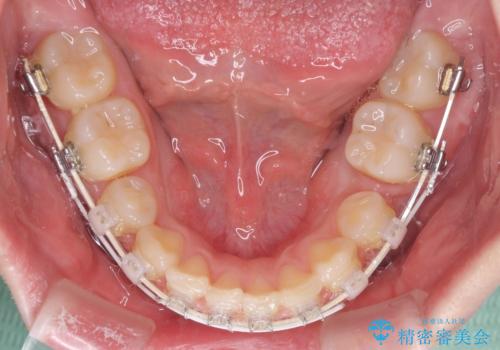

- 矯正装置

- 審美装置

- 八重歯と下顎小臼歯の欠損を気にして来院された患者様です。

下顎小臼歯の欠損により過蓋咬合となっていたため、下顎は臼歯を起こすことで咬み合わせを改善し、八重歯は第一小臼歯2本を抜歯し、補助装置を使用して速やかに改善することとしました。

八重歯は3,4か月で速やかに改善されました。